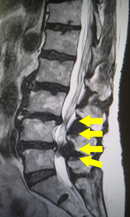

腰部脊柱管狭窄症のMRI画像。神経が複数箇所で狭窄を来している。